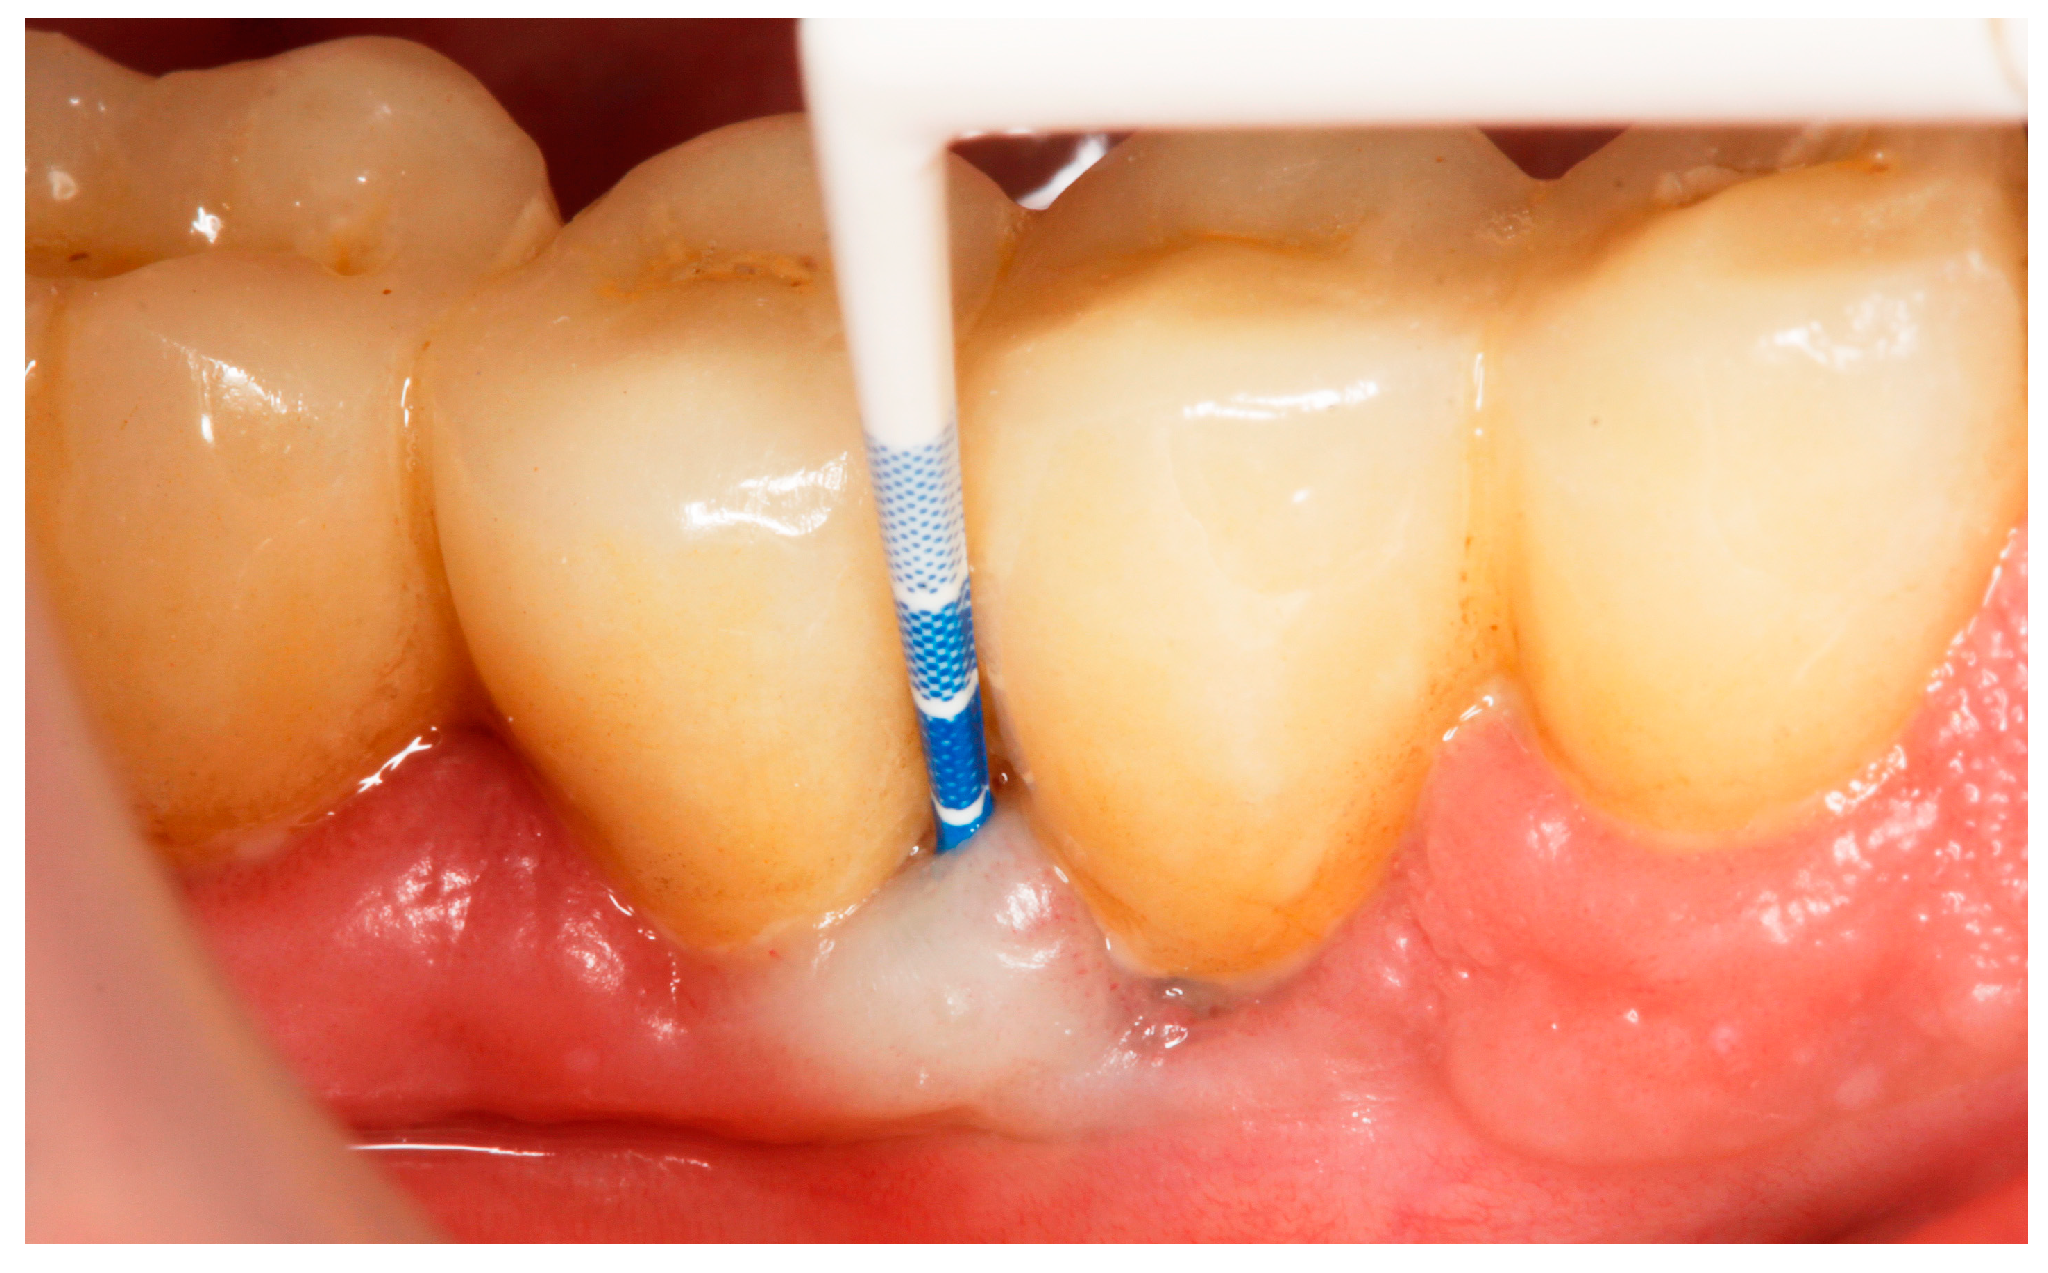

Baseline: Prior to PiM treatment, PMPR was performed in all subjects (Figure 3), for both teeth and implants. Each patient was assigned to one of the two treatment groups according to computer-generated randomization. One implant (the one with the greatest number of BoP points or the presence of a line of bleeding or profuse bleeding) with PiM in each patient was selected for the study. PMPR of the implants of interest was performed using an ultrasonic scaler with a plastic tip (Piezon® Master700 with Piezon® PI instrument, EMS, Nyon, Switzerland), and air polishing (Perioflow® handpiece, Airflow® PLUS powder, EMS, Nyon, Switzerland) was carried out at all sites. Piperacillin plus tazobactam gel Gelcide® (Italmed, Firenze, Italy) was prepared according to the manufacturer’s recommendations and was applied as follows: the solution was injected into the powder container, and the container was shaken until the solution became homogeneous. After mixing, the consistency of the mixture slightly increased, so it could be applied at the implant surface. Instrumentation was followed by subgingival application of the volatile mixture, depending on the patient’s group. For the Gelcide® group (test), topical application of Gelcide® was performed for the placebo group (control), topical application of a placebo (the volatile polymeric carrier alone) was carried out. The necessary quantity (not standardized) was then extracted from the mixed container with a syringe and inserted into the peri-implant sulcus at the apical extremity (Figure 4) until the excess became visible at the mucosal margin. Once the product had been applied, the excess was removed using a cotton ball.

Figure 4.

Application of Gelcide® in the peri-implant sulcus.